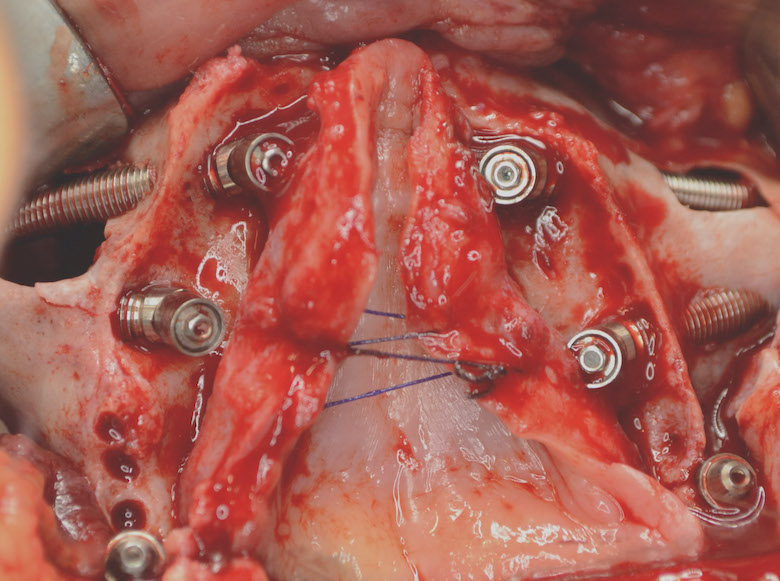

Restauración con implantes finalizada.